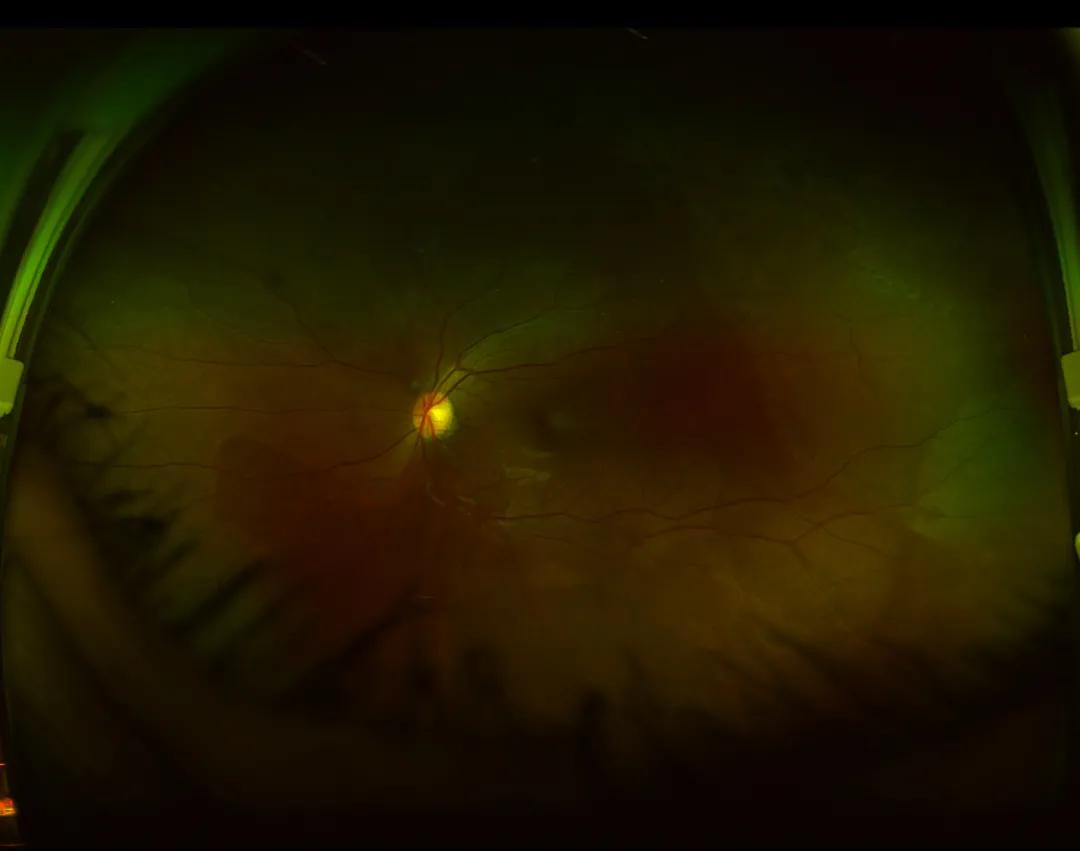

半个月后,小赛的左眼眼前出现固定黑影,发现异常的她请假来到浙江医院三墩院区眼科门诊, 浙江医院眼科洪明胜医师 简单了解病情后,通过眼部超声、欧堡广角彩照、裂隙灯下前置镜等检查,发现小赛左眼的视网膜周边2点钟方位有一个直径大小1mm的 视网膜裂孔,裂孔区视网膜浅脱离范围达到一个象限区域,急需手术治疗。

△(左图)眼部超声提示:左眼视网膜脱离;(右图)欧宝广角彩照检查:可以直观看到(右上角)颞上方视网膜脱离区域以及周边视网膜裂孔区。